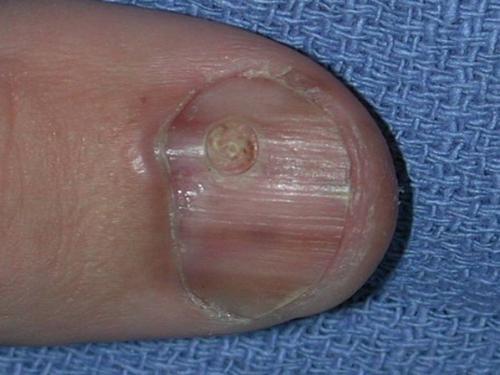

Подногтевая меланома I ст., 0,2 мм по Бреслоу

Признак II

Наиболее частым признаком этого вида меланомы является симптом Хатчинсона – переход пигментации на ногтевой валик или кончик пальца. На 7 из 8 изображений, представленных ниже, виден этот признак. В то же время нельзя однозначно утверждать, что этот симптом бывает только при меланоме. Он может наблюдаться и при прозрачной кутикуле .